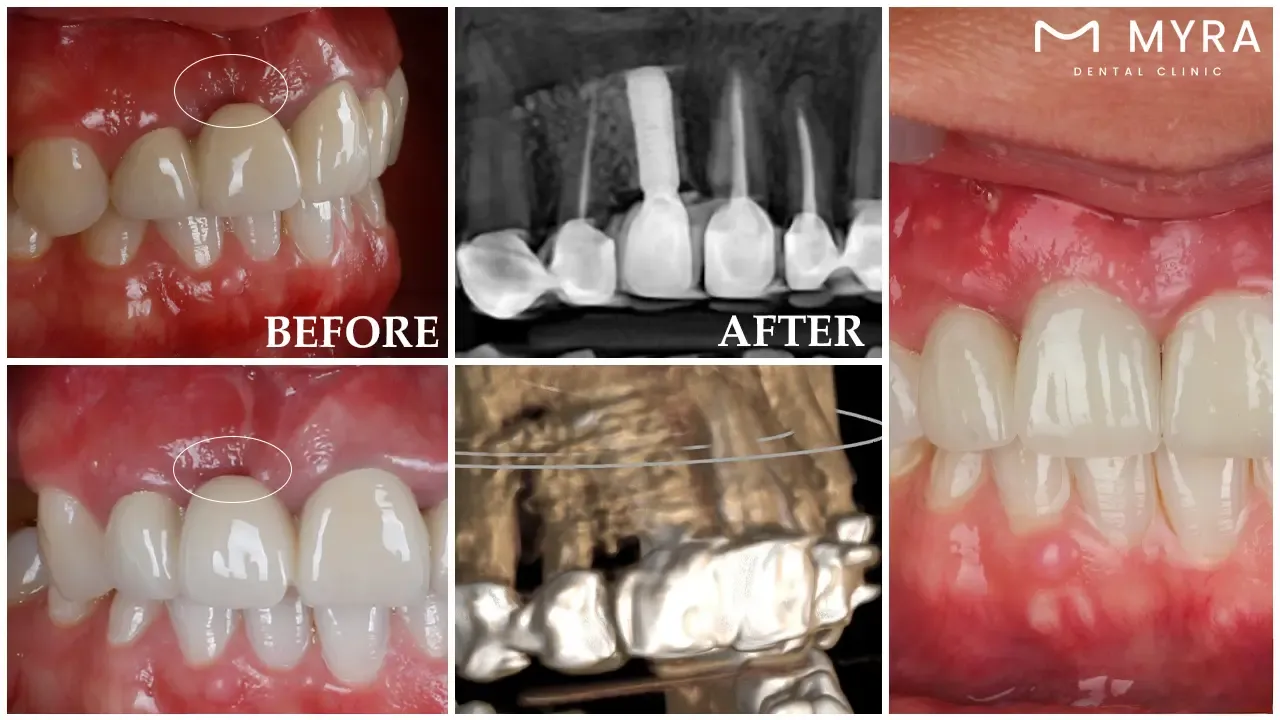

A dental implant for a single tooth is a surgical technique that involves the implantation of a titanium post into the jawbone. A dental implant for a single tooth is the best option for if one is missing a tooth or requires a tooth replacement in the near future. The post acts as a substitute for the tooth's root, which was lost when the tooth was extracted. After that, a crown is placed on top of the post to complete the creation of a false tooth that looks completely genuine.

A dental procedure known as an individual tooth dental implant is employed in order to restore a tooth's function and aesthetics as well as its look. An implant, a small titanium post, is surgically attached to the patient's jawbone as part of the operation. The post serves as the tooth's artificial root and gives the replacement tooth, commonly known as a crown, a solid basis. Osseointegration, a procedure that finally results in the implant becoming one with the jawbone, takes place. A reliable and robust connection between the two comes from it.

Implantation of Dental Implants: The dentist begins the surgical procedure to implant the dental implants, once the patient has made the decision to move forward with the process of getting dental implants. It requires the use of a local anesthetic to numb the region as well as a little incision to provide access to the jawbone in most cases. The dental practitioner uses a specialized drill to make a hole in the patient's jawbone, into which they place the dental implant, after that. The root of the tooth that is missing is replaced with an implant, which is a little post that looks like a screw and is composed of titanium or an alloy of titanium. The incision is closed by the dentist, and a protective covering is placed over the implant to make the healing process go more smoothly, after that.

Abutment Positioning: The healing process begins, once the implant has been successfully positioned. The procedure lasts anywhere from a few weeks to a few months, depending on the specifics of the patient's condition. The implant undergoes osseointegration, which is a procedure that causes it to merge with the jawbone during the time period. It gives a firm foundation for the dental crown. The protective cover is removed by the dentist, who then connects an abutment to the implant, after the implant has completed the integration process. The abutment is a relatively small connecting component that protrudes above the gumline and acts as the support for the dental crown. It is known as an abutment piece. It is possible for the dentist to take impressions of the abutment and the teeth that surround it in order to build a dental crown that is created to order and matches the size, shape, and color of the teeth that surround it.

Dental Crown Installation: The dentist proceeds to connect it to the abutment following the completion of the fabrication of the dental crown. The crown is often crafted from porcelain, ceramic, or a mix of the two materials in order to achieve both a long-lasting structure and a realistic appearance. The crown is tried in for both fit and bite by the dentist, who then makes any required changes before dental cement is used to permanently secure it in place. The dentist goes through post-operative care instructions with the patient following the placement of the crown. The instructions include topics such as dental hygiene procedures, food restrictions, and follow-up appointments to check on the progress of the implant.